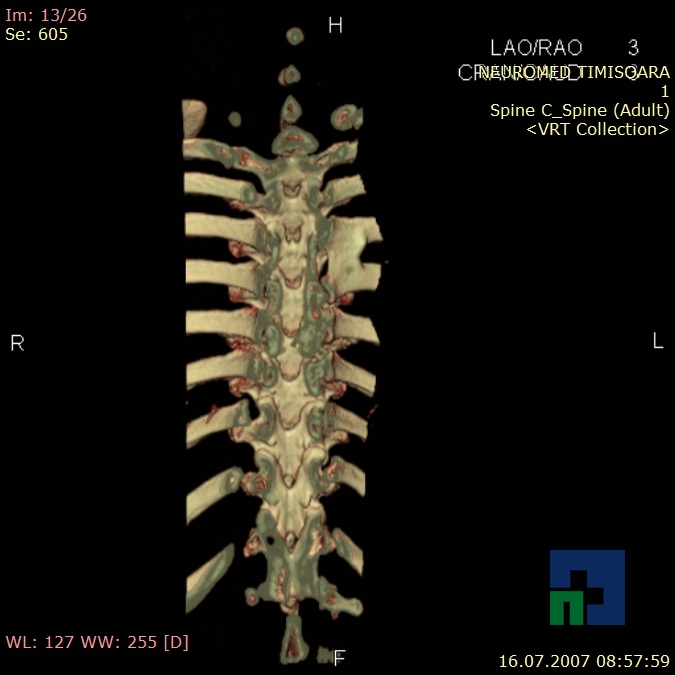

Examinare de rutină cerebrală, nativ și cu substanță de contrast (SDC) pentru diagnosticul:

- Diagnosticul fracturilor:

- Unice

- Multiple

- Cu înfundare

- Complexe cranio-sinusale

- Complexe cranio-etmoidale

- Complexe cranio-orbitare

- Complexe cranio-faciale